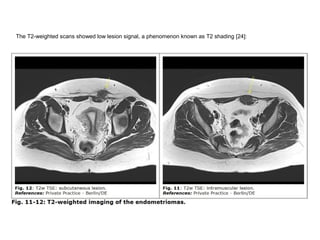

The T2-weighted scans showed low lesion signal, a phenomenon known as T2 shading [24]:

Furthermore, in all performed scans but especially in the inversion recovery scans (TIRM) the lesion showed small